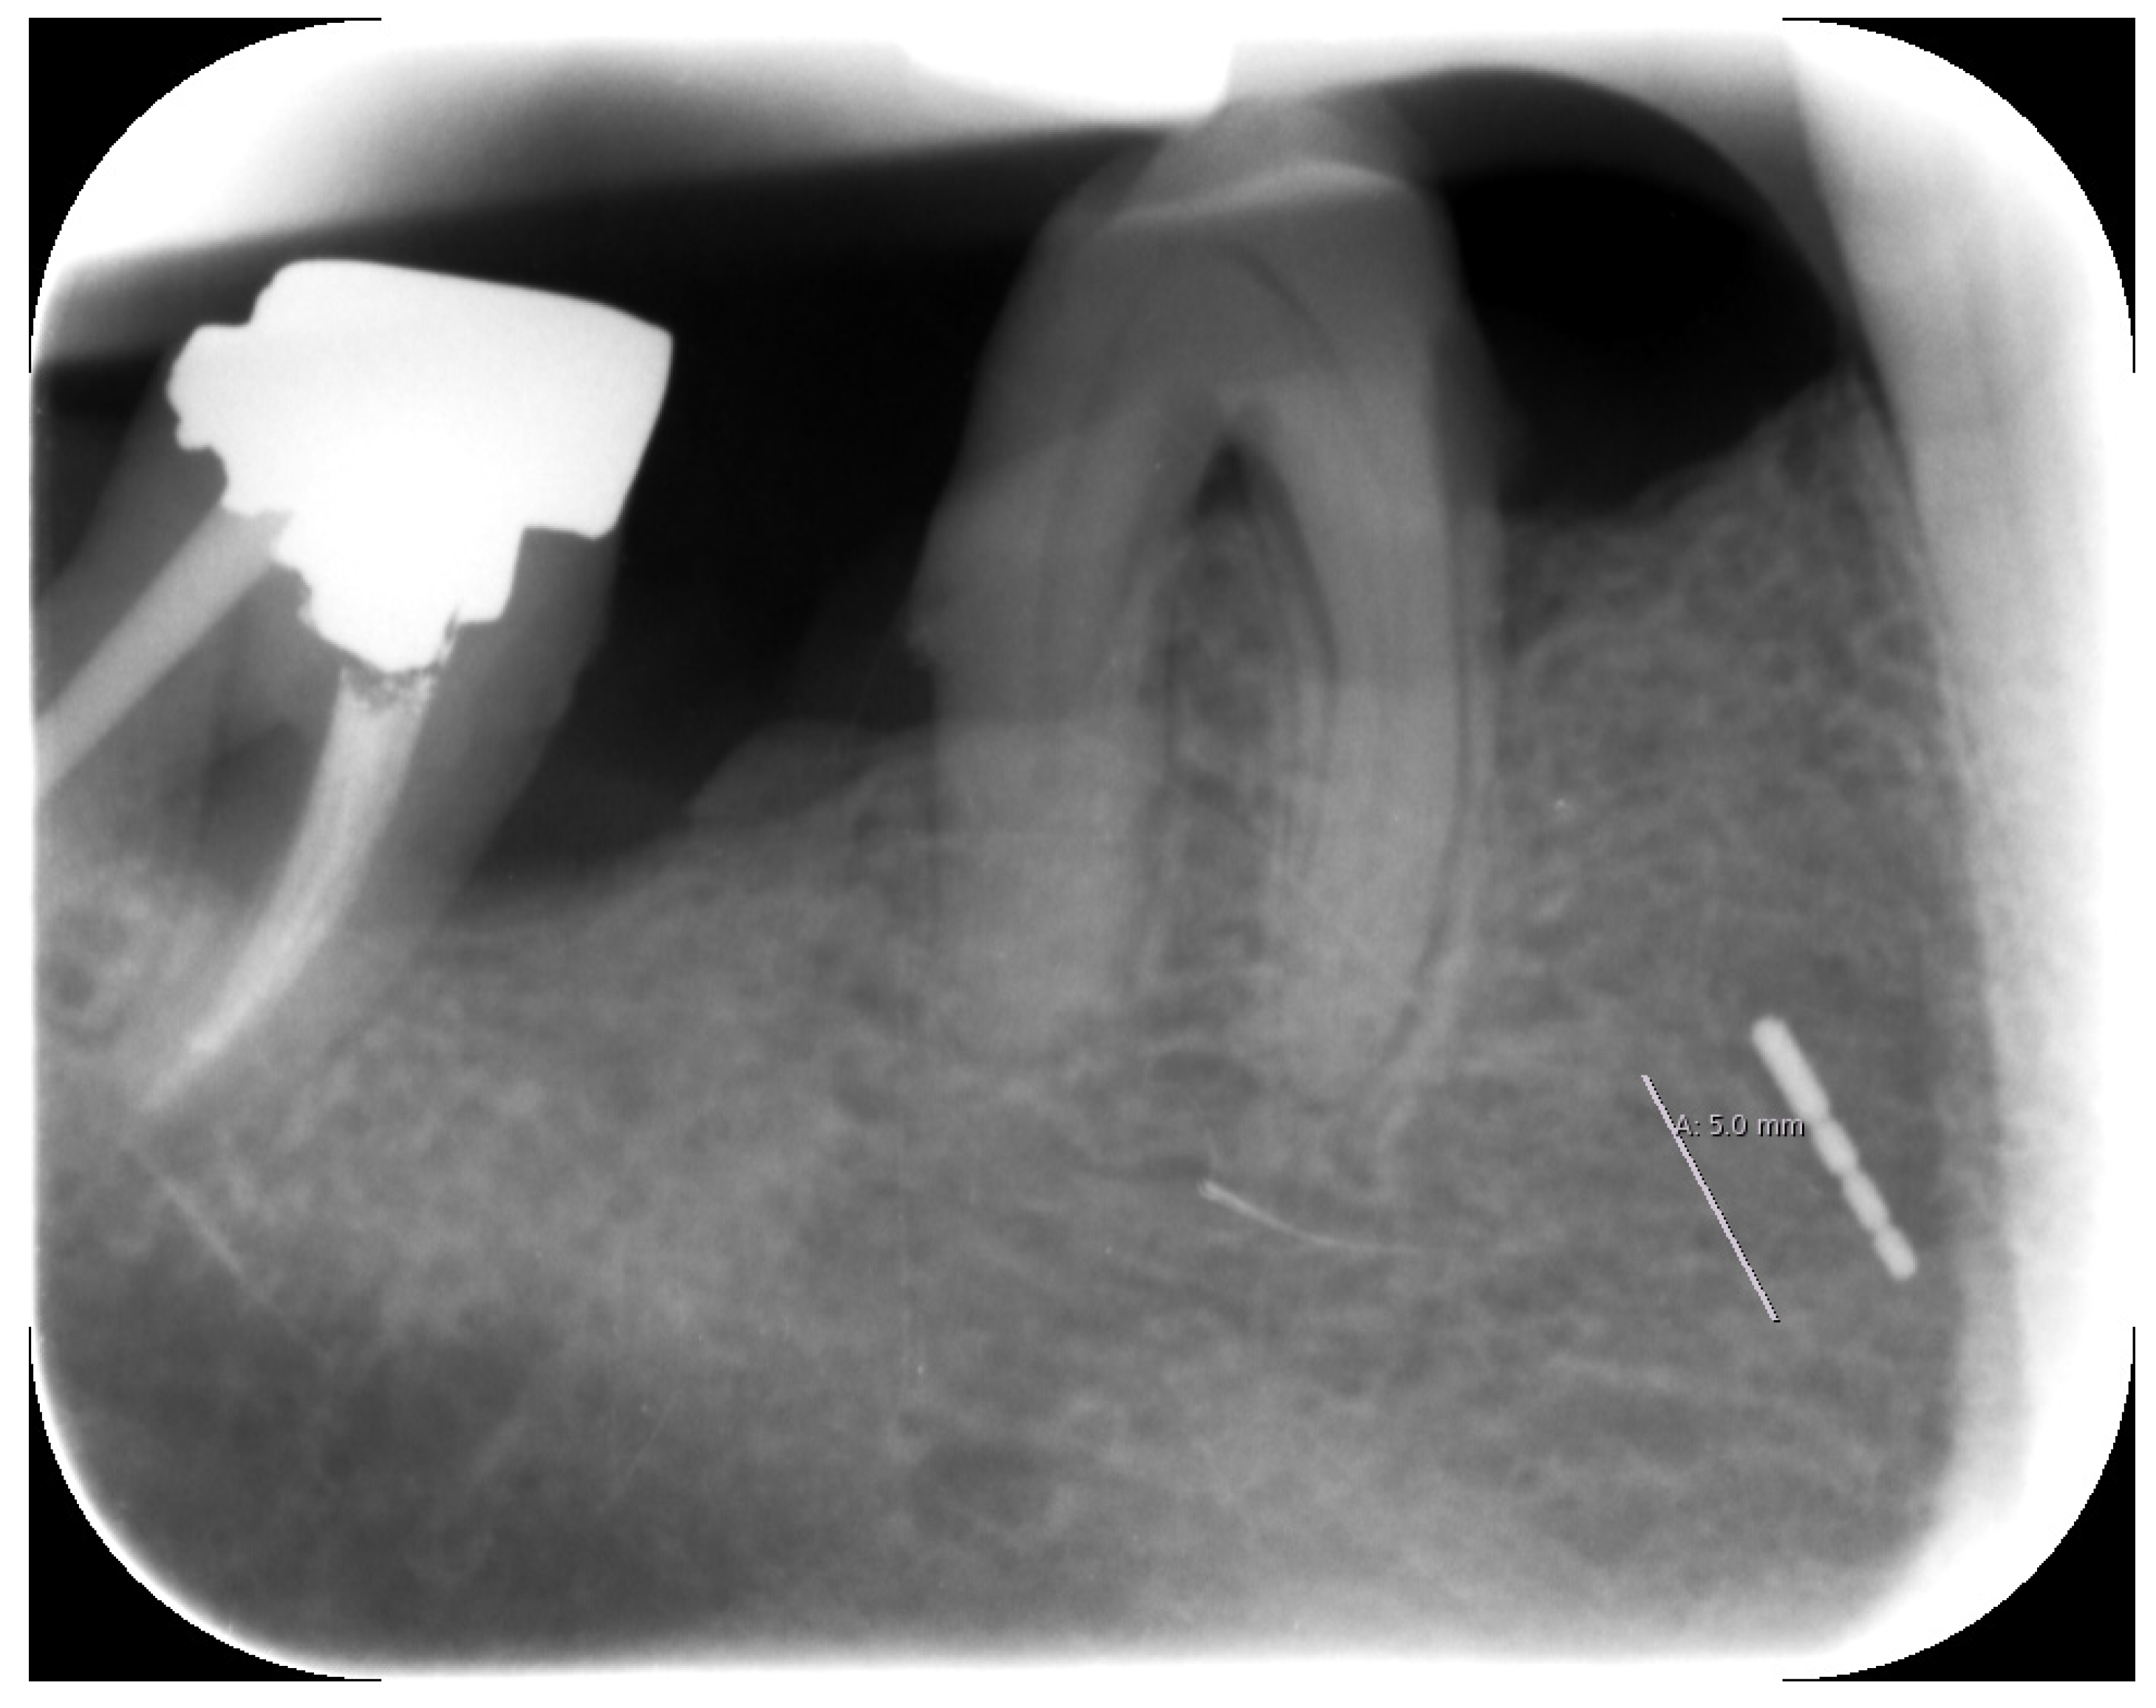

Region 45 showed a thin cylindrical, approximately 5 mm (coronal-apical) metallically dense opacity in the OPT (Figure 1).

Figure 1.

Orthopantomogram taken in October 2019.

2.3. X-ray

Unfortunately, no older X-rays were available. The single tooth X-ray taken in our clinic in December 2019 clearly identified the broken periodontal probe in two dimensions (Figure 3).

Figure 3.

Periapical X-ray with the broken periodontal probe.